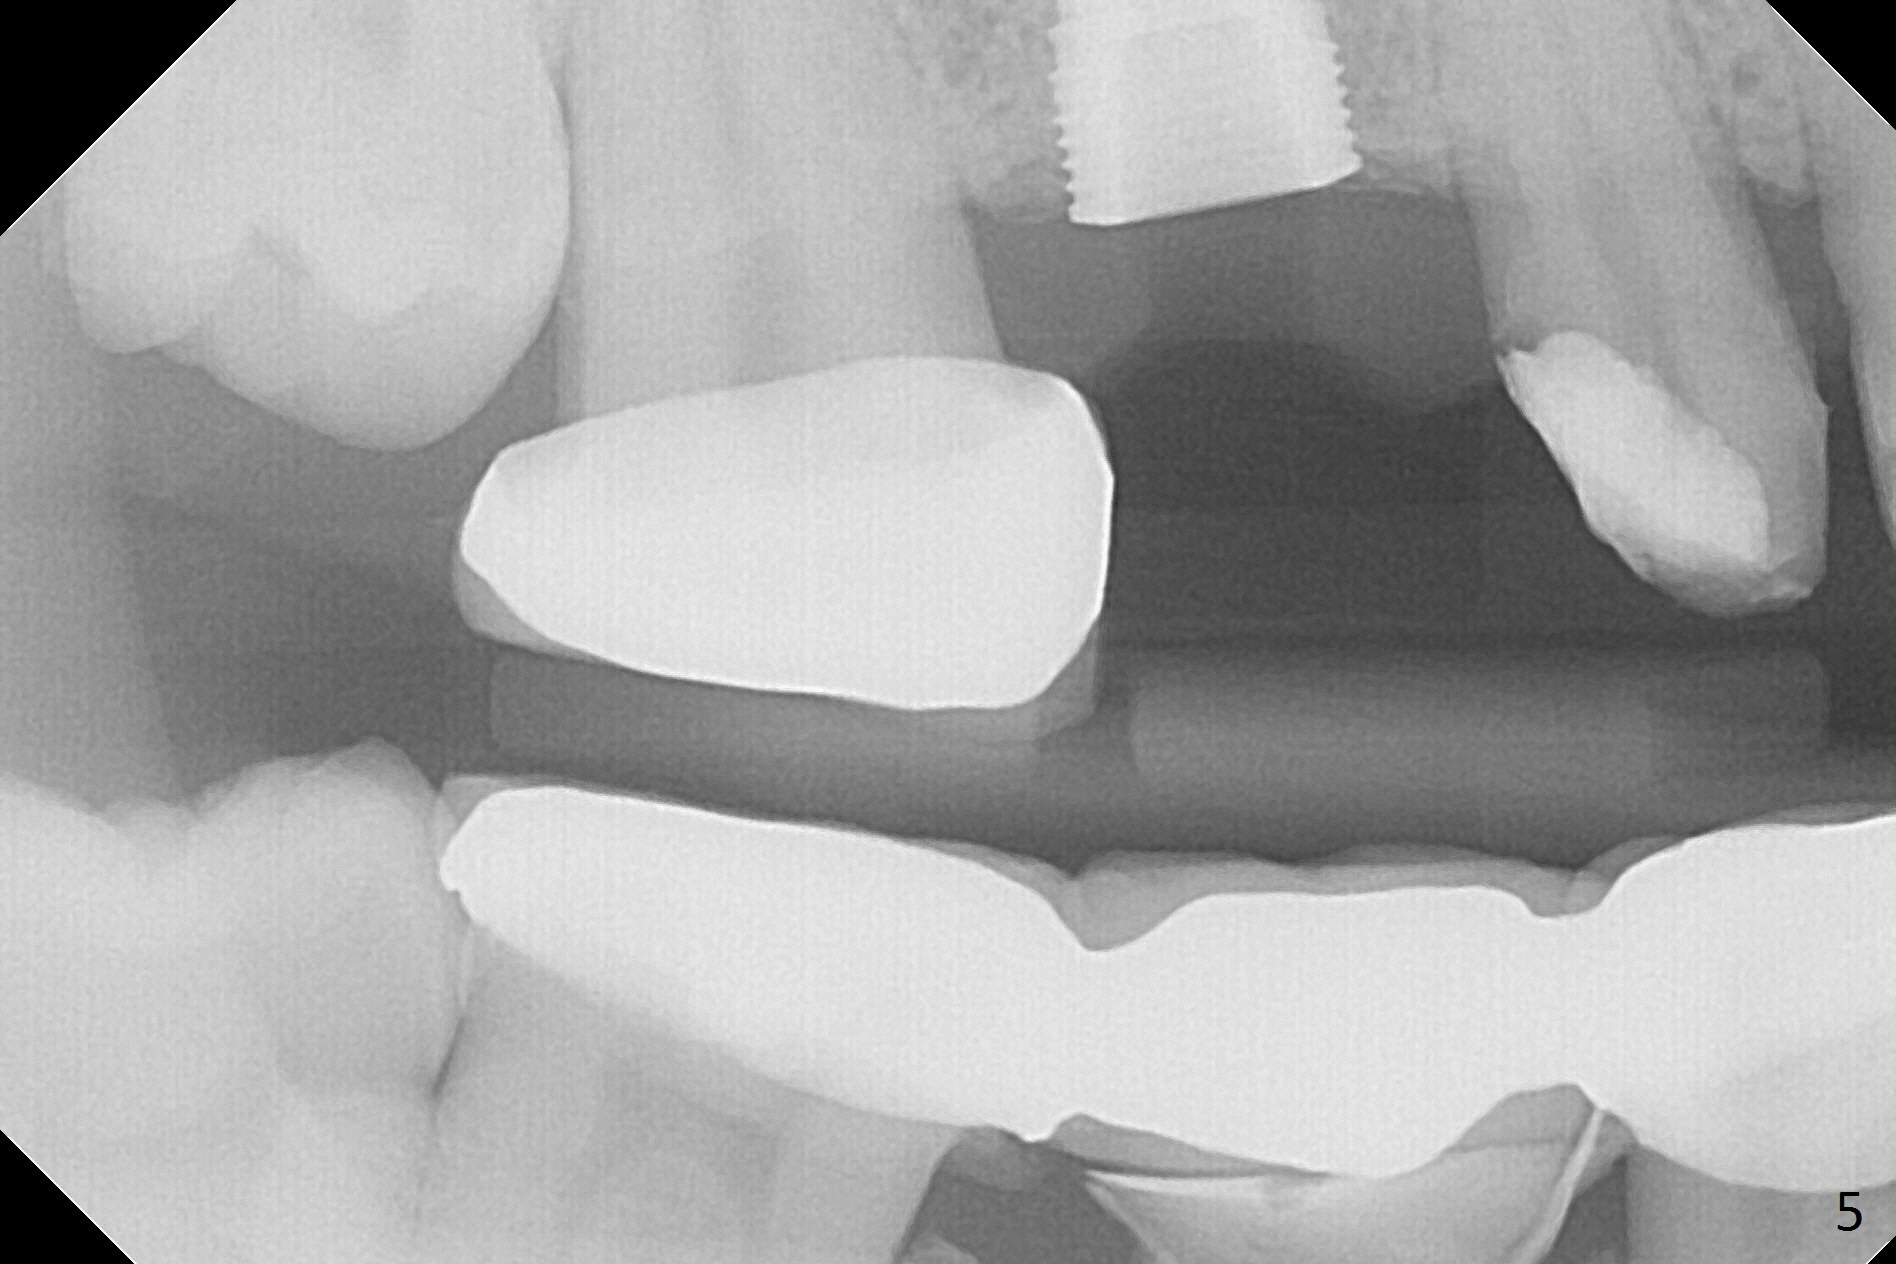

When the bridge is partially removed, the tooth #4 is found to have extensive caries. IRM is placed following carious removal (Fig.1). Magic Split testing shows that the bone density is high (flapless). Osteotomy is initiated by 1.6 mm drill, but the handle of the drill needs to shift mesial (Fig.1 red arrow). When the latter is done, the whole drill (2 mm) needs to move distal (Fig.2 double red arrows). When a 4.5x14 mm drill finishes the osteotomy, it is in the middle of the edentulous space (Fig.3). After use of 5 mm tap, a 5.3x14 mm implant cannot reach the depth (Fig.4,5). Following increase in osteotomy depth from 16 to 18 mm (gingival margin) until 5 mm drill in diameter, the implant placement level is more ideal (Fig.6,7, slightly subcrestal) with insertion torque maintaining at >55 Ncm. The sinus floor (Fig.4 arrowheads) may be penetrated when the osteotomy depth increases (Fig.7 *), but the sinus membrane remains intact.